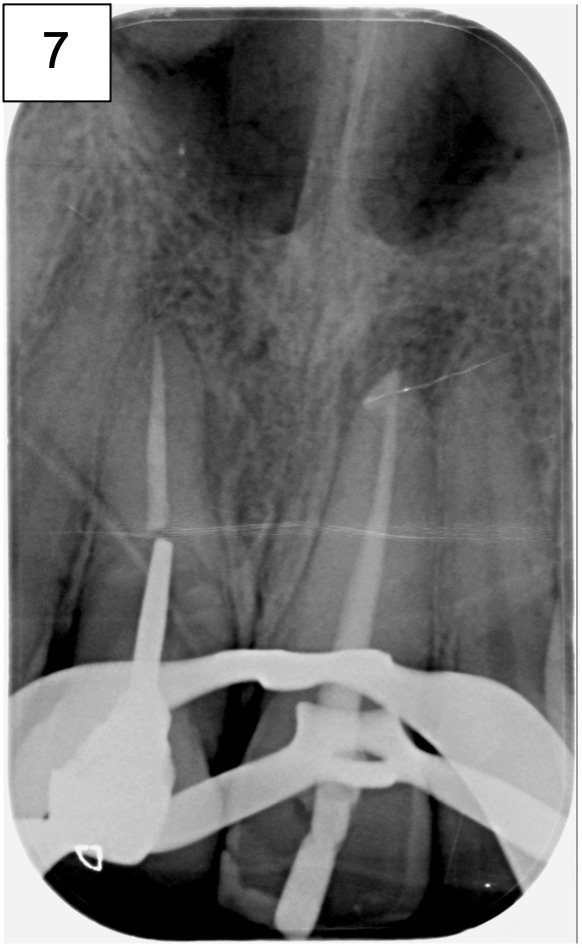

• Bilan rétro alvéolaire (Photo 3)

La radiographie rétro alvéolaire, met bien en évidence la présence d’une lésion au niveau du tiers médian radiculaire de cette 11.

Au niveau de 21, une lésion apicale est présente et un test au froid négatif confirme la nécrose de la dent et la nécessité de la réalisation d’un traitement endodontique.